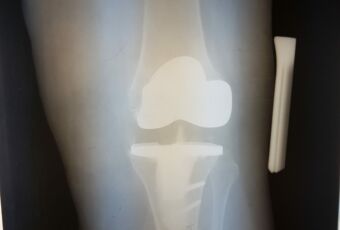

- Наименование операции: ревизионное эндопротезирование коленного сустава.

- Используемое оборудование, методика: использовался специальный установочный инструментарий для имплантации полусвязанного эндопротеза коленного сустава LCCK Zimmer, методика операции: удаление нестабильного компонента тотального эндопротеза коленного сустава, подготовка поверхностей костной ткани к имплантации ревизионного компонента, примерка компонентов эндопротеза, установка ревизионных связанных компонентов при помощи костного цемента. Операция – ревизионное эндопротезирование коленного сустава связанным эндопротезом.

- Краткая информация о пациенте, диагноз: Пациентка С., 1952 г.р. Диагноз: Асептическая нестабильность компонентов эндопротеза левого коленного сустава.

- Краткое описание хода операции (основные этапы): Иссечены рубцовые ткани по периферии сустава. Удален полиэтиленовый вкладыш и два винта с шайбами из бугристости большеберцовой кости. Затем с помощью долот и набойников удалены последовательно бедренный и большеберцовый компоненты. По направителям произведены минимальные опилы большеберцовой и бедренной костей. Затем развертками обработан канал большеберцовой кости до размера 14 мм, а бедренной кости до 17 мм. Имплантированы примерочные компоненты на интрамедуллярных ножках, отмечены дефекты, требующие заполнения металлическими блочками и стабильность сустава. После этого на 1 дозу костного цемента имплантированы бедренный компонент («Е») LCCK с ножкой 100/17 мм, большеберцовое плато 4 с ножкой оффсетной 100/14 мм, вкладыш LCCK 14 мм, 3 металлических блочка. Сустав вправлен, стабилен.

- Результат: имплантация ревизионного эндопротеза коленного сустава.